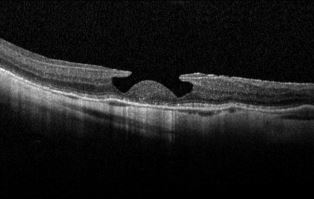

Μερικού πάχους οπές ωχράς κηλίδας

Σε αντίθεση με τις ολικού πάχους οπές της ωχράς, όπου η παθοφυσιολογία, η διαγνωστική προσέγγιση και οι ενδείξεις χειρουργικής παρέμβασης είναι εν πολλοίς ξεκάθαρες και κοινώς αποδεκτές, οι οπές μερικού πάχους παρουσιάζουν μεγαλύτερη ετερογένεια ως προς τους μηχανισμούς και τα χαρακτηριστικά τους, ενώ τα διαγνωστικά τους κριτήρια, η κατηγοριοποίηση και ο σχεδιασμός της βέλτιστης αντιμετώπισης…